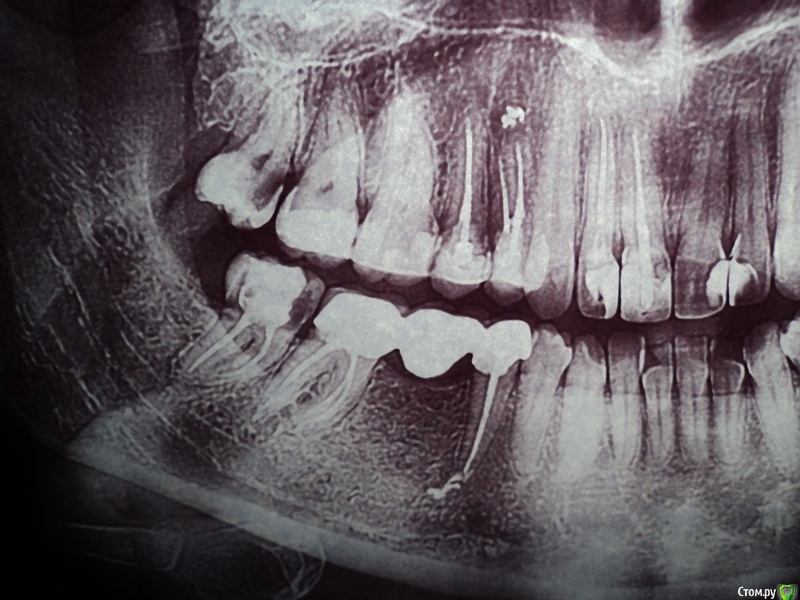

Анэйтис Опубликовано 5 февраля, 2015 Поделиться Опубликовано 5 февраля, 2015 (изменено) Добрый день!Четыре года назад мне были удалены 36 и 46 зубы (шестые нижние). Поставили мосты. Недавно начал ныть 37 зуб (нижний левый).Мост слетел. В 37 зубе - вторичный кариес. К тому же этот зуб, как выяснилось - наполовину пломба, наполовину сам дентин. Я опасаюсь, что если начать его лечение, остатки дентина могут отколоться до десны. И мост поставить будет, грубо говоря, не на что. Какие варианты лечения есть в таком случае? Можно ли сделать вкладку и на нее установить мост снова? Будет ли надежной такая конструкция, учитывая то, что зуб - жевательный. Очень хотелось бы услышать ваше мнение по поводу ситуации с 35, 37 и 45, 47 зубами.И еще очень интересуют 18, 28, 38, 48 зубы - удалять или еще что-то можно спасти? Изменено 5 февраля, 2015 пользователем Анэйтис Ссылка на комментарий

SDC Опубликовано 5 февраля, 2015 Поделиться Опубликовано 5 февраля, 2015 Добрый день!Четыре года назад мне были удалены 36 и 46 зубы (шестые нижние). Поставили мосты. Недавно начал ныть 37 зуб (нижний левый).Мост слетел. В 37 зубе - вторичный кариес. К тому же этот зуб, как выяснилось - наполовину пломба, наполовину сам дентин. Я опасаюсь, что если начать его лечение, остатки дентина могут отколоться до десны. И мост поставить будет, грубо говоря, не на что. Какие варианты лечения есть в таком случае? Можно ли сделать вкладку и на нее установить мост снова? Будет ли надежной такая конструкция, учитывая то, что зуб - жевательный. Очень хотелось бы услышать ваше мнение по поводу ситуации с 35, 37 и 45, 47 зубами.И еще очень интересуют 18, 28, 38, 48 зубы - удалять или еще что-то можно спасти? Здравствуйте.Снимок, который Вы предоставили слишком контрастный, по этому снимку можно запросто ошибиться с первичной диагностикой кариеса зубов, но похоже, что 8-е зубы сохранять просто незачем.Тем не менее, правильным вариантом будет:имплантация в области отсутствующих нижних 6-х зубов и одиночные коронки на 5-е и 7-е зубы.Стоит подумать о протезировании коронками 15, 14, 25 зубов. Ссылка на комментарий

Анэйтис Опубликовано 16 февраля, 2015 Автор Поделиться Опубликовано 16 февраля, 2015 У меня в 37 - очень большая пломба. Практически на 2/3 зуба. Сам этот зуб (37) - опорный под мостиком (37 - 35). Между пломбой и самой тканью зуба по стенке - кариес. Можно ли поставить в него культю и на нее снова "посадить" мост назад? Будет ли такая конструкция надежной? Ссылка на комментарий

Saymon Опубликовано 20 февраля, 2015 Поделиться Опубликовано 20 февраля, 2015 (изменено) У меня в 37 - очень большая пломба. Практически на 2/3 зуба. Сам этот зуб (37) - опорный под мостиком (37 - 35). Между пломбой и самой тканью зуба по стенке - кариес. Можно ли поставить в него культю и на нее снова "посадить" мост назад? Будет ли такая конструкция надежной?1. Нужно определиться с самими зубами. Перелечивать или нет. Для этого нужны прицельные снимки.2. Определиться с методом восстановления культи зуба, после перелечивания(культевая вкладка, либо просто пломба).3. Выбрать вариант восстановления зубов:а) изготовить в любом случае новые мостовидные протезы. Старые можно выкинуть. ИЛИб) изготовить отдельно стоящие коронки на зубы, которые были под мостами и установить имплант с коронкой в область отсутствующего зуба.4. Восьмерки удалять.P.S. Подзамазать, подшаманить и посадить мост обратно технически можно, но не надолго. И через некоторое время варианты лечения будут другие, а это бОльшое количество имплантов или съемные протезы и никаких мостов. Изменено 20 февраля, 2015 пользователем Saymon Ссылка на комментарий